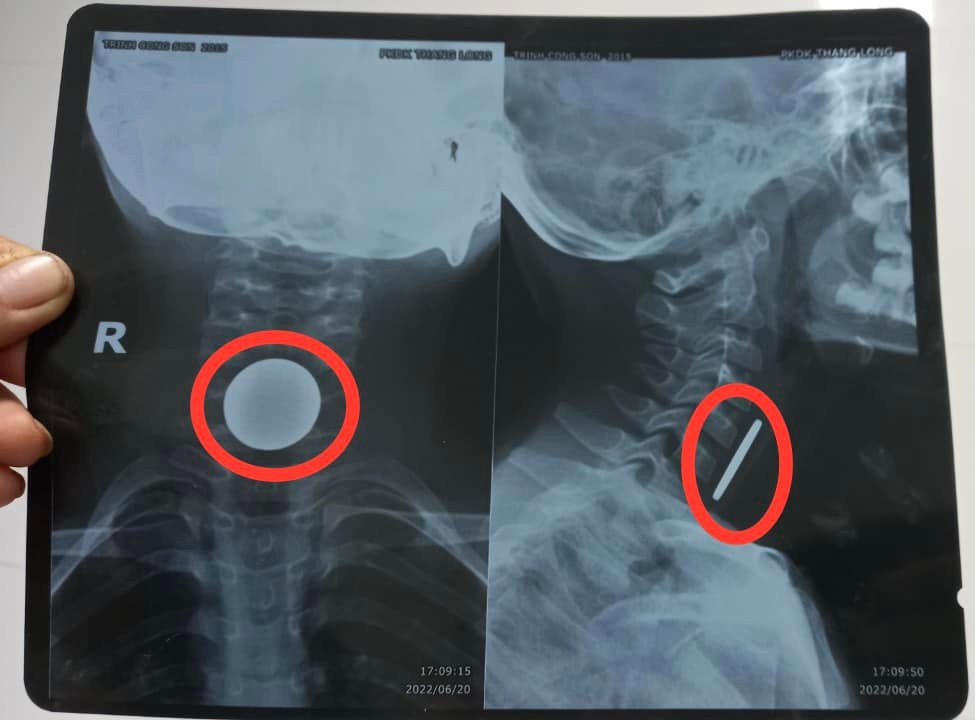

Tại Khoa Cấp cứu, các bác sĩ thăm khám và nghi ngờ có dị vật thực quản. Bệnh nhân được chụp X-quang và kết quả cho thấy có dị vật hình tròn cản quang nằm ngang đoạn 1/3 trên thực quản. Sau khi hội chẩn, bệnh nhân được chỉ định phẫu thuật nội soi can thiệp gắp dị vật đường tiêu hoá trên ( gây mê) và chuyển lên khoa Thăm dò chức năng để tiến hành.